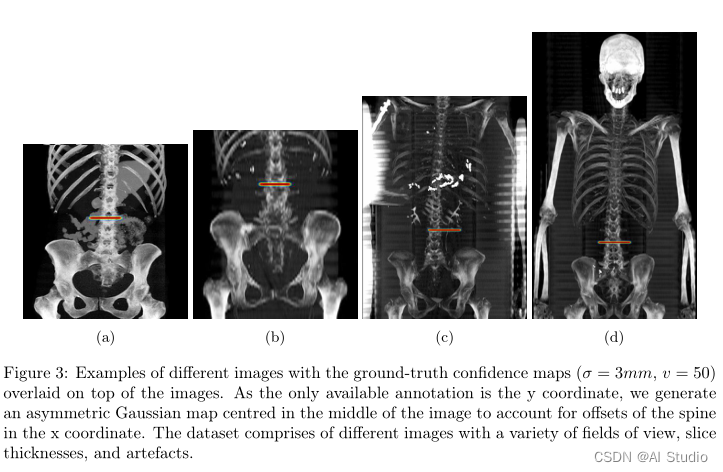

对归一化为1x1mm的图像进行注释。MIP图像由2名注释员注释:一名具有7年经验的放射科医生和一名具有5年CT图像工作经验的注释员。

对于每个图像集,注释器都会看到正面和受限矢状MIP并排显示,注释器单击L3切片的位置。

主要标志物被选为椎弓根的中间,与横突的顶部边缘对齐。